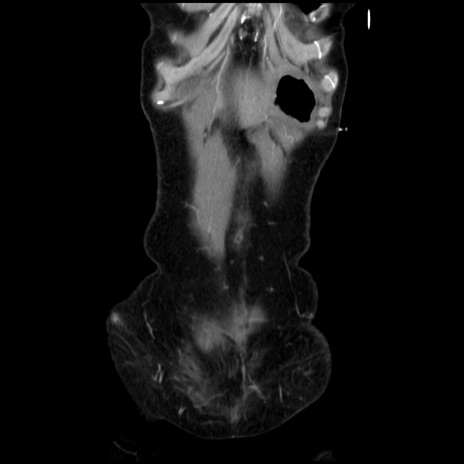

症例32(冠状断像)

【症例】40歳代 女性

【主訴】上腹部痛、嘔気・嘔吐

【現病歴】約9時間前頃から急に上腹部痛、嘔気、嘔吐が出現。改善しないため救急要請。

【既往歴】子宮頚癌(広汎子宮全摘術、放射線療法)、腸閉塞

【身体所見】腹部:平坦、軟、腸雑音亢進、上腹部を中心に腹部全体に圧痛あり。

【データ】WBC 8400、CRP 0.03